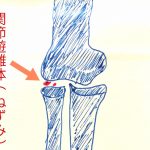

関節遊離体(関節ネズミ)について

こんにちは。所沢接骨院の伝法です。 関節ネズミとは主に肘、足首、膝の関節に骨軟骨骨折や裂離骨折による 骨片が挟まってしまい、関節がロッキング(曲げ伸ばし不能)になるものです。 関節ネズミの名前の由来は、 関節の中に隠れている様や中で少し動いている様から この名前を用いるようになったとも言われています。 症状 関節の可動域制限 痛みが無いことが多い 原因 肘で……続きを読む